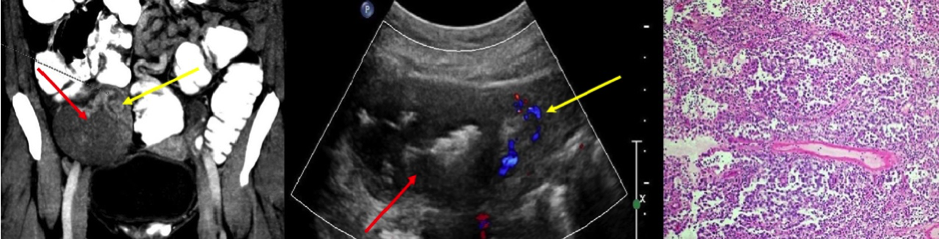

Poster abstracts – FPM Centenary Conference – 7th December 2018

14c

940 × 240 pixels